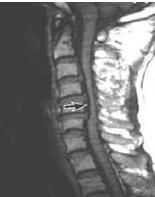

3.CT及CTM檢查;

4.MRI檢查;

6.CT檢查

可見矢狀徑小於12mm,有向後延伸的骨刺等,一般取腰4-5,腰5-骶1的小關節水平攝CT片。